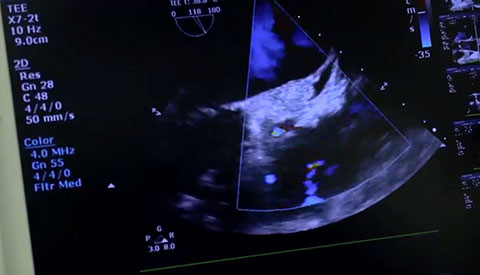

تم تشخيص أحد المرضى لديك بتضيّق في الصمام الأورطي المصحوب بأعراض. يبلغ عمر المريضة 85 عامًا وهي تعاني من السكري وارتفاع ضغط الدم. أنت تدرك خطورة وضعها الصحي ما يجعلها غير مناسبة لجراحة القلب ولكن يسمح لها بأن تكون مرشحة لاستبدال الصمام الأورطي باستخدام القسطرة (TAVR). في يومنا هذا، تمنح حلول التصوير المبتكرة والأجهزة التي تعمل عن طريق الجلد الأمل لبعض المرضى الذين لا تتوفر لهم حتى الآن أي خيارات علاجية أخرى.